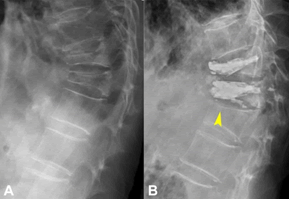

Journal-Neurological-Disorders-91-year-old

Figure 3. A 91-year-old man with vertebral compression fracture treated with SpineJack®. T11, T12, two different stages of thoracolumbar spine lateral X-rays, (A) pre-OP, (B) new occurrence of anterior superior endplate fracture at L1 within 1 month (yellow arrowhead).